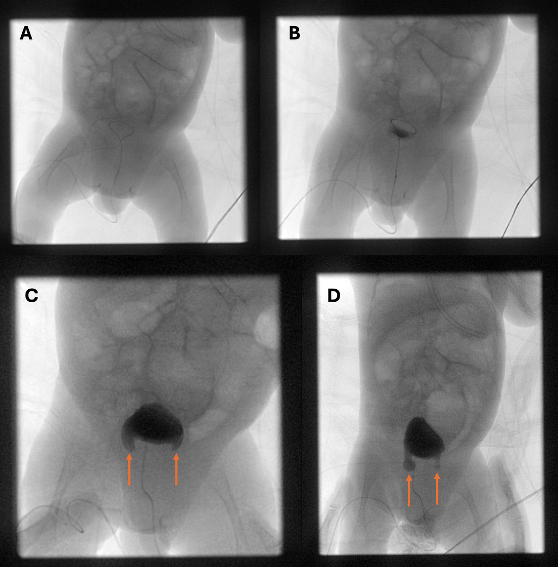

Diagnostic Testing. Catheterized urine cultures confirmed more than 100,000 colony-forming units of Klebsiella on two separate occasions. A renal and bladder ultrasound (RBUS) initially showed mild left-sided hydronephrosis, a minimally distended bladder, and otherwise normal renal parenchyma. He then underwent a voiding cystourethrogram (VCUG) for further assessment of the urinary tract, which incidentally revealed bilateral bladder herniations into the inguinal canals, without vesicoureteral reflux or urethral anomalies (Figure 1). The bladder emptied nearly completely at the end of the study with spontaneous bladder-containing inguinal hernias resolution.

Figure 1. Voiding cystourethrogram: (A) scout image without contrast; (B) partial bladder filling with no apparent abnormality; (C, D) bilateral bladder containing inguinal hernias, no vesicoureteral reflux.